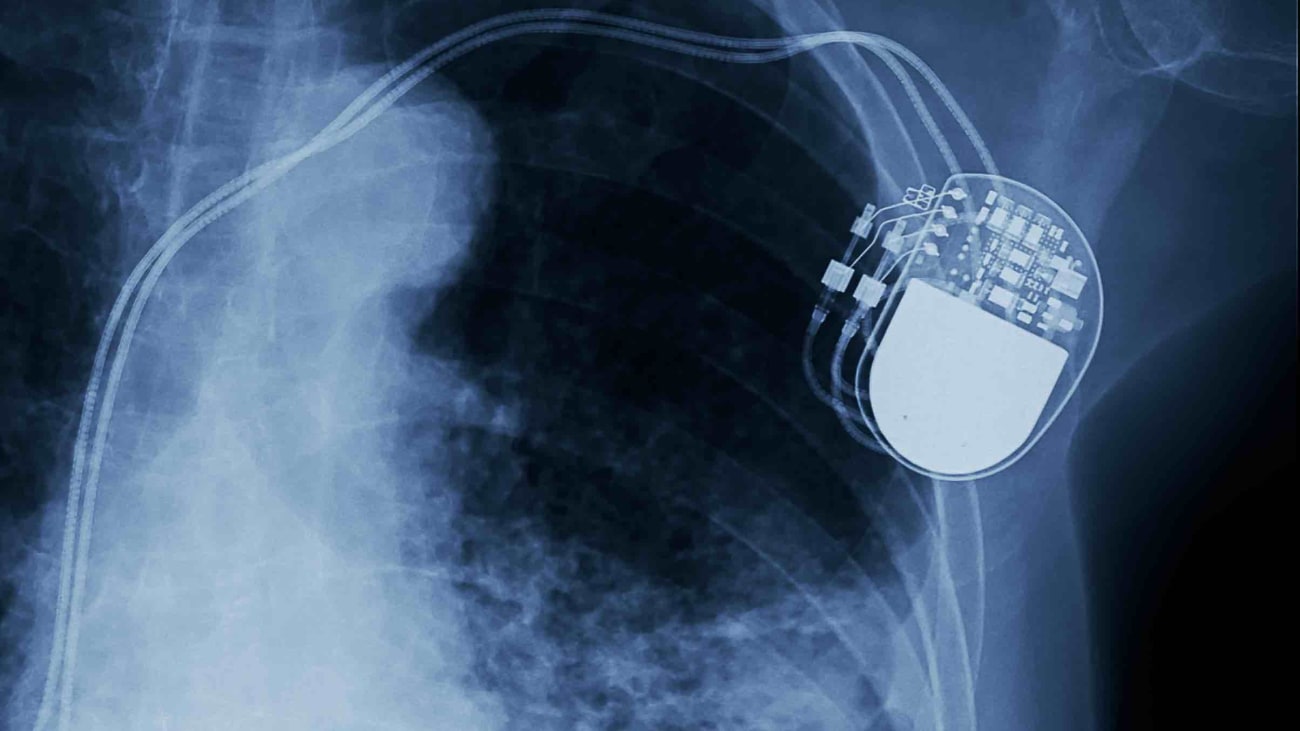

Advanced Heart Failure and VADs in the Community